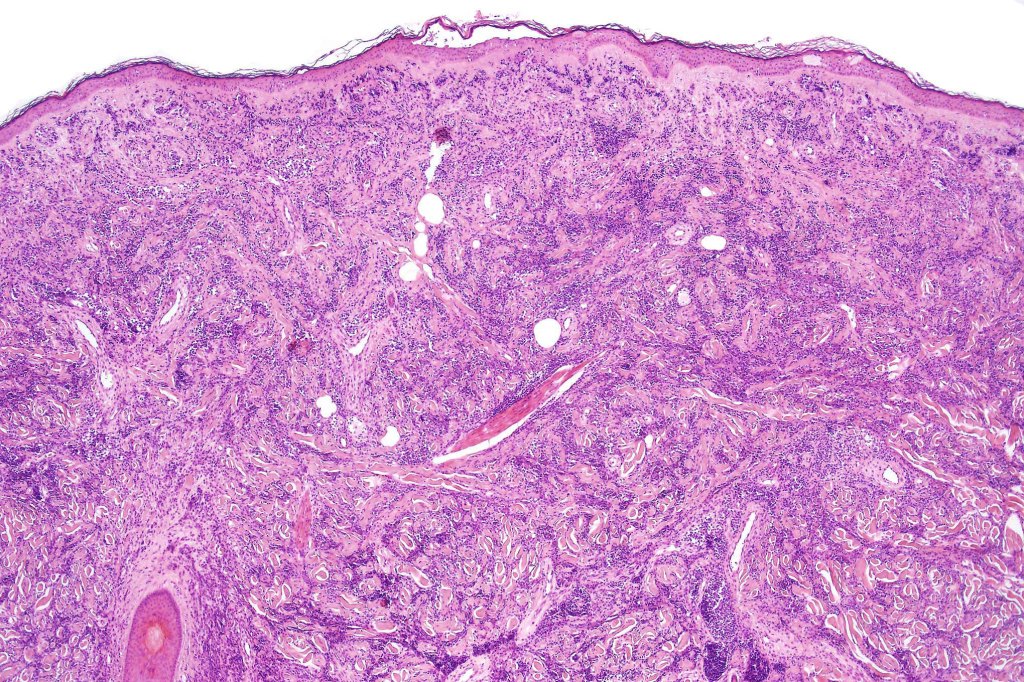

A rare variant of nevoid melanoma wherein the tumor cells have scant cytoplasm, and basophilic, hyperchromic nuclei mimicking type B nevus cells. Typically, the tumor cells are positive for S100, Mart-1 & HMB45. It is of no prognostic importance. It is one of the more often encountered melanoma variants in giant congenital nevi & can be mistaken for a congential nevus if the lesion is dismissed as benign at scanning magnification. In the absence of clinical history in metastatic lesions, the differential diagnoses of lymphoblastic leukemina/lymphoma, neuroendocrine carcinoma, small cell carcinoma, neuroblastoma, malignant perihperal nerve sheath tumor & Ewing’s sarcoma can be excluded with appropriate immunohistochemistry. Exceptionally small cell melanoma may express neuroendocrine markers